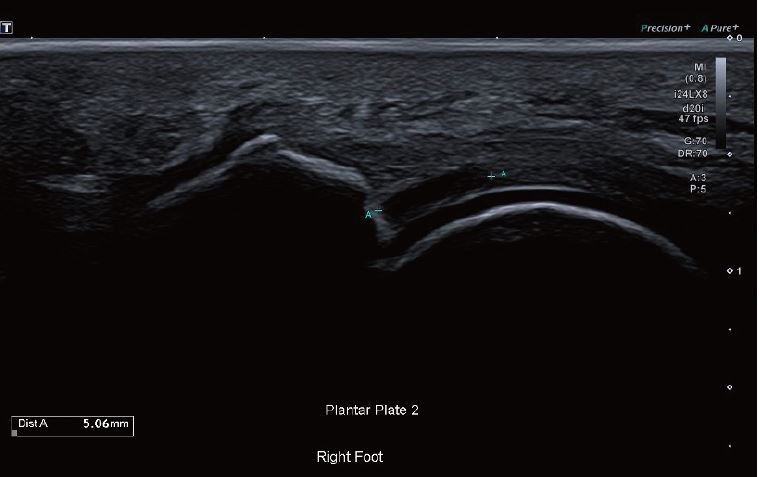

Зображення 1 Поздовжній знімок другої плантарної пластини демонструє

розрив 5 мм.